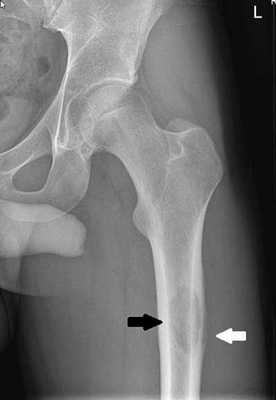

Остеохондрома на рентгенограмме представлена в виде дополнительной тени, соединенной с костью ножкой или реже — широким основанием. Растет в сторону от сустава, медленно, но может достигать больших размеров. Контуры остеохондромы бугристые, неровные. Кортикальный слой в виде тонкой окаймляющей пластинки прослеживается на всем протяжении опухоли. Иногда корковое вещество лучеобразно направлено к поверхности опухоли. Обращает внимание сочетание мелких участков деструкции (хрящевая ткань) с наличием трабекулярного рисунка и массивных вкраплений известковых теней. При больших размерах остеохондром наблюдаются деформации соседних костей. Например, выраженное искривление и деформация кортикального слоя малоберцовой кости при больших размерах остеохондромы большеберцовой кости. Мы наблюдали также раздвигание и деформацию ребер при остеохондроме ребра у ребенка 11 лет.

Остеохондрому приходится дифференцировать с одиночными и множественными костно-хрящевыми экзостозами, которые относятся к дисплазиям. В длинных трубчатых костях костно-хрящевые экзостозы располагаются в области метафизов, и по мере роста как бы сдвигаются к диафизу. Костно-хрящевые экзостозы имеют многообразную форму, окружены компактной костной пластинкой, которая переходит с основной кости. Структура экзостозов напоминает структуру трубчатой кости. У линейных экзостозов с выраженной ножкой хрящевой «колпачок» определяется на его вершине; при шаровидной форме экзостоза хрящ находится по всей сферической поверхности. Он может обызвествляться, и на рентгенограммах определяются известковые включения, часто менее выраженные, чем при остеохондроме, В пользу костно-хрящевых экзостозов следует отнести полиоссальность. поражения и аномалии развития костей, часто наблюдающиеся при дисплазии.

Остеохондрома может озлокачествляться. Известны озлокачествления остеохондром лопатки и костей таза, остеохондром длинных трубчатых костей. Мы наблюдали малигнизацию остеохондром ребра (I), плечевой кости (I), короткой трубчатой кости стопы (I). Эти изменения характеризуются появлением сильной боли, разрушением кортикального слоя, выраженной деструкцией и дополнительной мягкотканной тенью за пределами остеохондромы. Лечение остеохондромы — хирургическое.